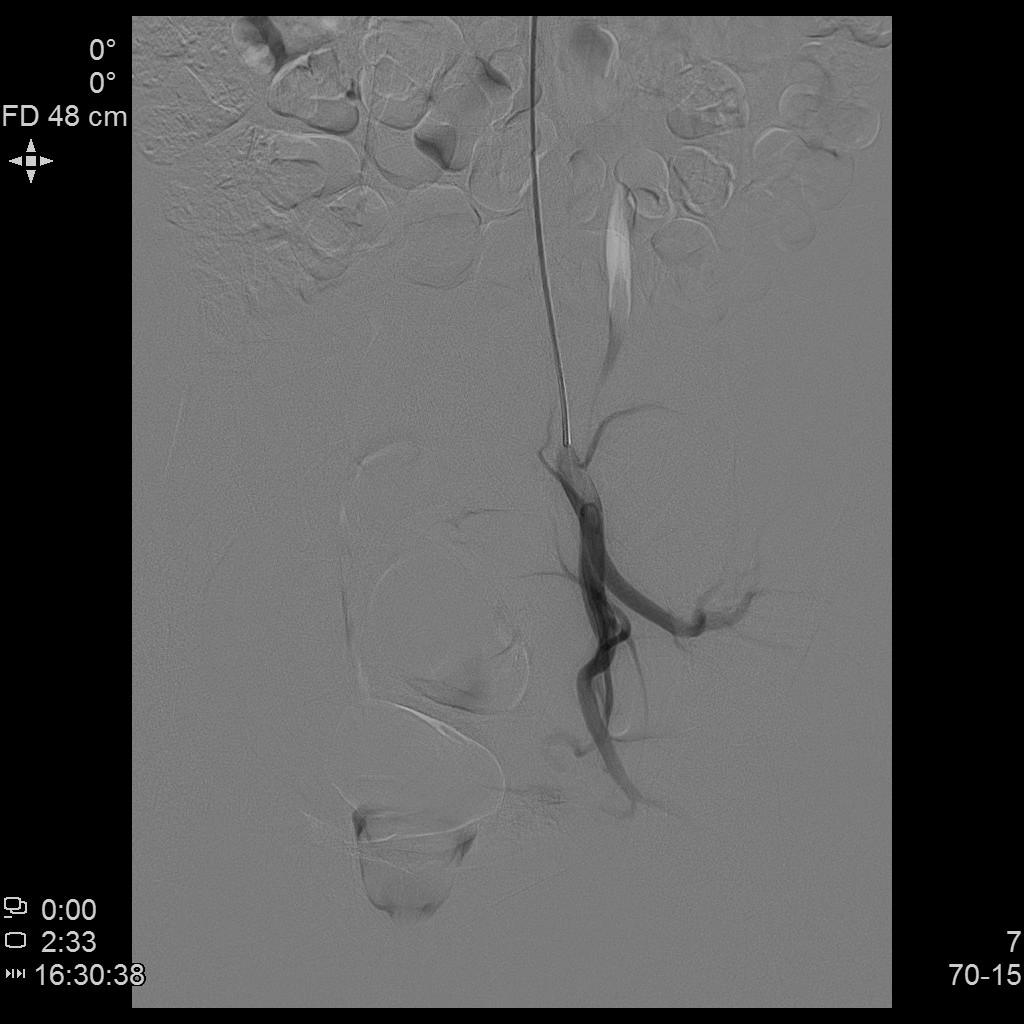

- 进一步超选插管左侧子宫动脉造影确认位置

- 微导管进一步超选插管左侧子宫动脉主干造影确认位置

- 栓塞术后复查造影显示左侧子宫动脉分支末梢未见显示